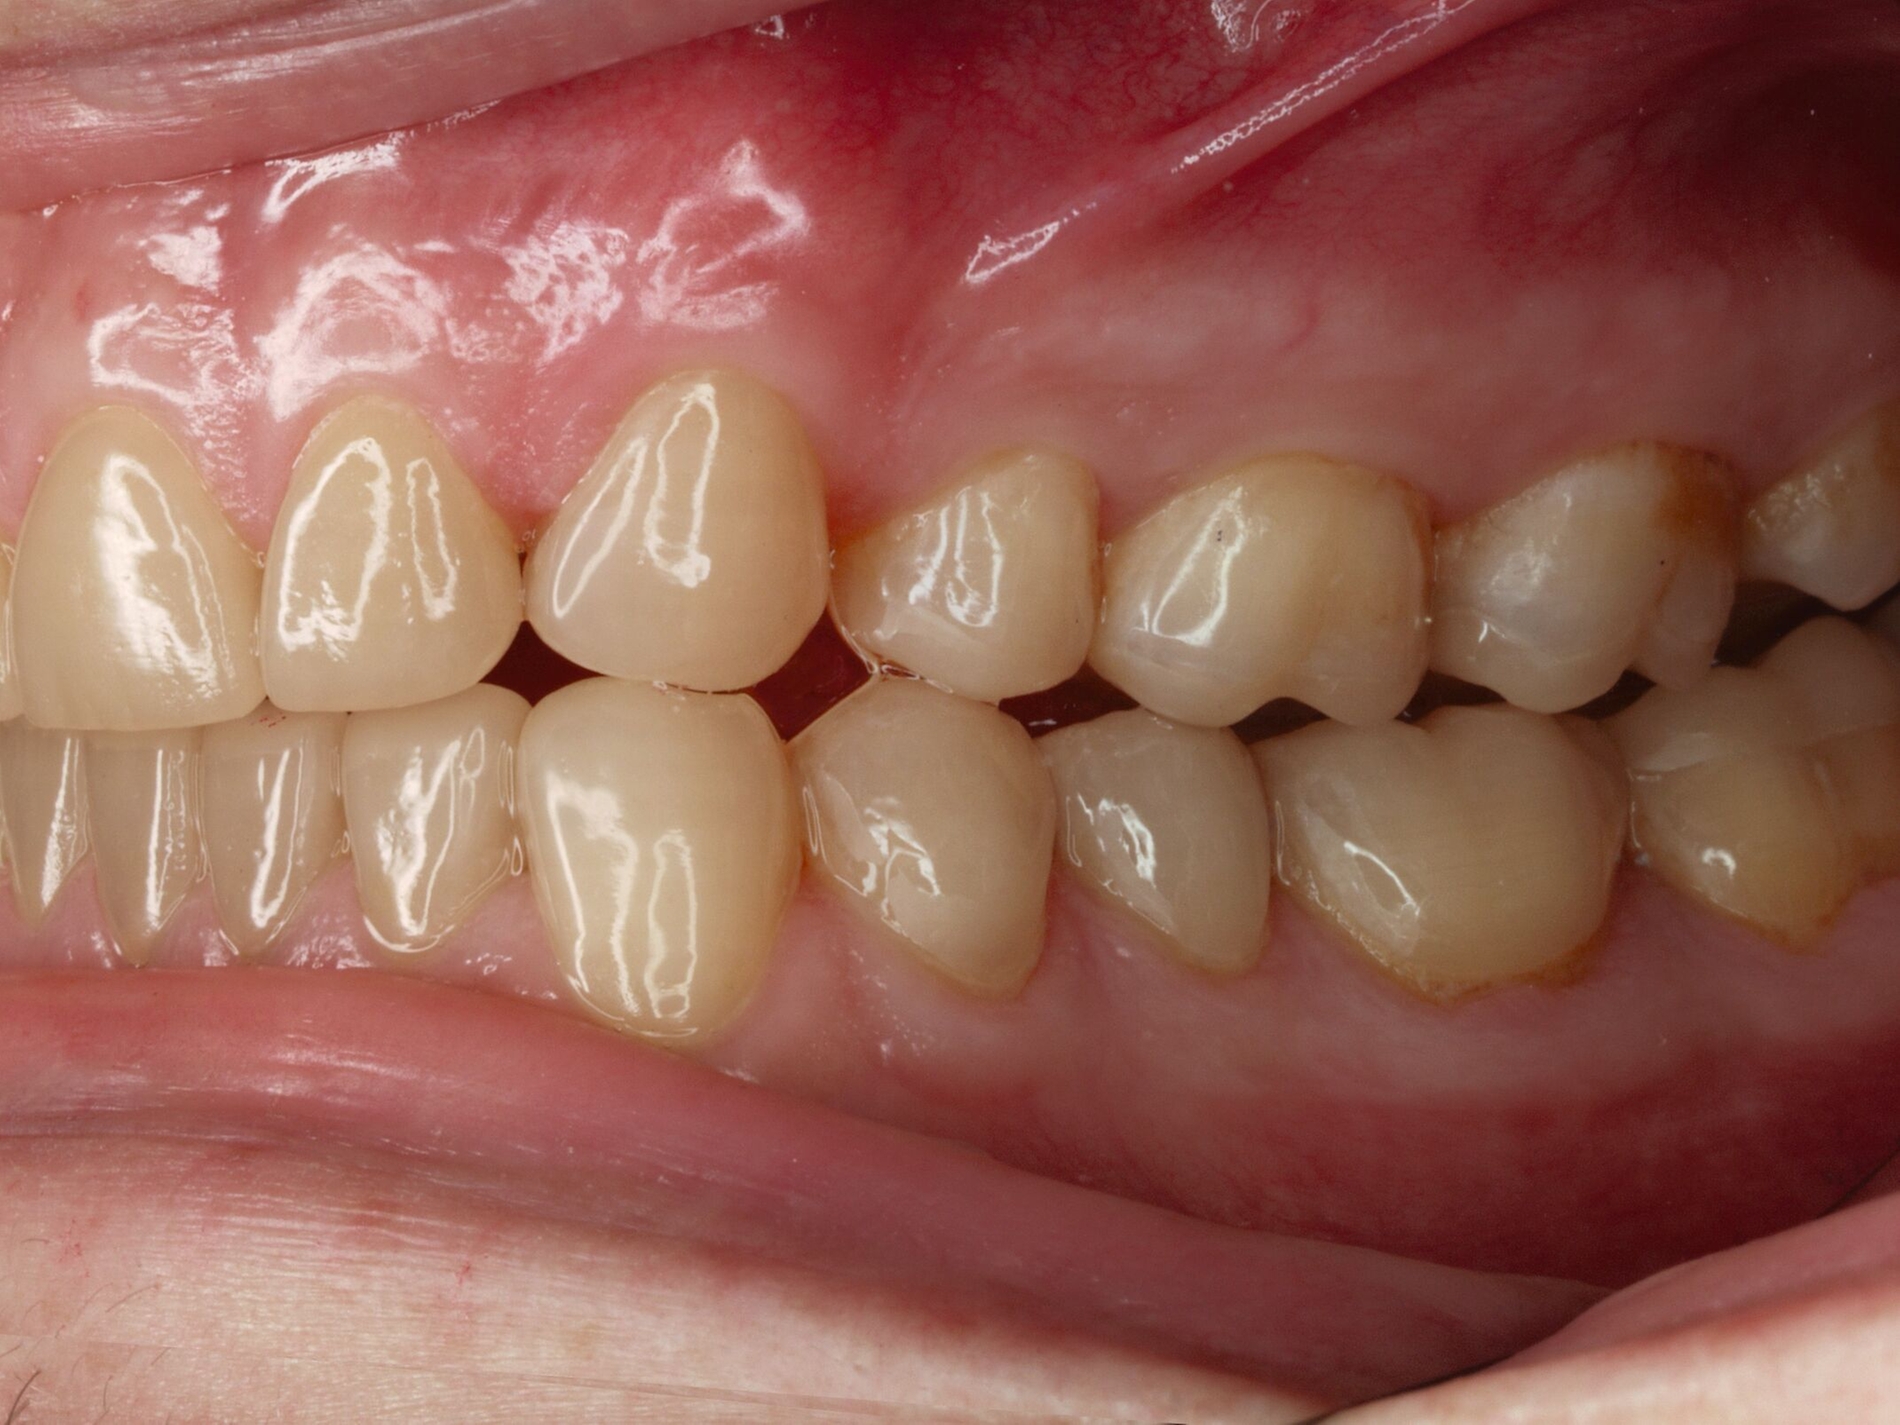

Das unter Beteiligung des Autors entwickelte Tooth Wear Evaluation System (TWES) 2.0 [Wetselaar et al., 2020] identifiziert per Screening Patienten mit erhöhten Verschleißwerten, vergleichbar mit dem PSI in der Parodontologie oder dem CMD-Kurzbefund. Bei auffälligen Werten folgt ein differenzierter Zahnverschleiß-Status einschließlich der Erfassung oraler und vestibulärer Substanzverluste [Wetselaar et al., 2016 sowie von Pathologie-Symptomen und einer strukturierten Diagnose [Tonetti und Sanz, 2019; Wetselaar, 2020]. Den Einsatz in der Praxis illustriert der in den Abbildungen beschriebene Patientenfall aus dem CMD-Centrum Hamburg-Eppendorf.

Im Unterschied zum Zahnverschleiß-Screening wertet der Zahnverschleiß-Status den höchsten Verschleißgrad pro Zahn aus, und zwar okklusal/inzisal, oral und vestibulär (Abbildungen 4b und 4c, Tabelle 1). Wichtig für die Planung therapeutischer Maßnahmen ist die Frage, welche Zähne okklusal in Kontakt stehen, denn die Behandlung von Zähnen mit erheblichem Zahnverschleiß lässt keinen weiteren Substanzverlust zu und erfordert bei Zähnen in Kontakt absehbar eine Erhöhung der vertikalen Dimension der Okklusion.

Im Beispiel ist daher die Diagnose ein generalisierter erheblicher und lokalisierter moderater pathologischer Zahnverschleiß überwiegend mechanischer und zudem chemischer Ursache. Die sich daraus ableitende Erkenntnis ist, dass in allen Sextanten Zähne freiliegende Dentinkerne aufweisen (generalisierter moderater Zahnverschleiß), dass darüber hinaus Zähne erheblich geschädigt und somit gefährdet sind, dass Merkmale eines pathologischen Geschehens bestehen – und dass als Ursache neben dem dominierenden Bruxismus ein Säureeinfluss hinzukommt.

Auch wenn Restaurationen nach Möglichkeit vermieden werden sollten, ist deren Verfügbarkeit für die Betroffenen individuell höchst wichtig, weil sie bestehende Schmerzen beseitigt, die verlorengegangene Kauleistung wiederherstellt und ästhetische und nicht zuletzt auch phonetische Einschränkungen aufhebt. Bei dem in den Abbildungen beschriebenen Fall korrelierte der erhebliche Zahnverschleiß mit der Lokalisation der Zahnschmerzen des Patienten. Direkte Restaurationen mit Kompositen hatten keinen Bestand. Die durchgeführte restaurative Behandlung hingegen hat Bestand, die Schmerzen waren danach umgehend verschwunden und sind seit zehn Jahren nicht wiedergekehrt.

Dabei führt die Verfügbarkeit hochfester Dentalkeramiken heute zu viel weniger invasiven Restaurationen als früher durchgängig übliche metallkeramische Kronen, und die Transluzenz der keramischen Werkstoffe ermöglicht zudem natürlichere Restaurationen. Der beschriebene Behandlungsfall zeigt, wie eine mehrstufige Zahnverschleiß-Diagnostik im Praxisalltag umgesetzt wird, mit initialem Zahnverschleiß-Screening und einer im Bedarfsfall erfolgenden erweiterten Diagnostik per Zahnverschleiß-Status.